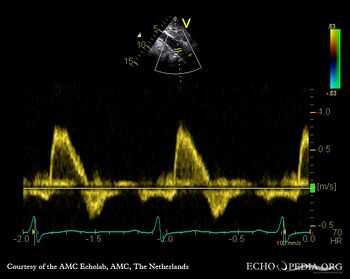

Abdominal Aortic Doppler Waveform In Patients With Aorto ...

Abdominal Aortic Doppler Waveform in Patients with Aorto-iliac Disease G. Styczynskia,*, C. Szmigielskia, J. Leszczynskib, A. Kuch-Wociala, M. Szulca ... Return Document